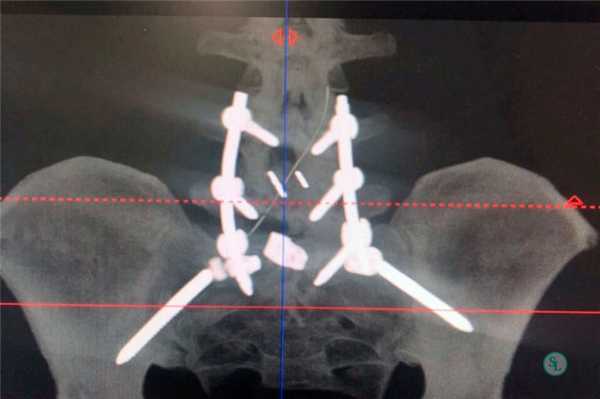

Перед установкой транспедикулярных винтов, на противоположной от резецированного сустава стороне, выполняется декортикация дуг, поперечных отростков для создания условий формирования спондилодеза. С помощью общепринятых анатомических и рентгенологических ориентиров выполняется транспедикулярная фиксация.

Траектория установки винта в аксиальной плоскости (а), проекция точки введения винта на задние отделы позвоночника (б), траектория установки винта в сагитальной плоскости (в).

Для введения транспедикулярных винтов используется наиболее доступная и распространенная методика freehand, однако требует от хирурга соответствующего мастерства. С целью более безопасного введения винтов и избежание их мальпозиции используется навигационное оборудование и интраоперационный нейрофизиологический мониторинг.

ТПФ выполняется под рентгеновским контролем, что позволяет хирургу точно контролировать каждое движение и избежать повреждения близкорасположенных анатомических структур. Чаще для этого используется ЭОП или КТ.

Очень важно при установки винтов соблюсти следующие моменты: отсутствие пространства между костью и винтом, исключение травматизации нервных и сосудистых структур или смежных дугоотросчатых суставов. Импланты устанавливаются согласно размерной линейки каждого позвонка и винта, бикортикально не касаясь замыкательных пластин.

Точка установки винта в корень дуги подбирается на основании расположения двух анатомических ориентиров - поперечного и суставного отростков позвонка. Непосредственно позвонок перфорируют с помощью специального зонда.